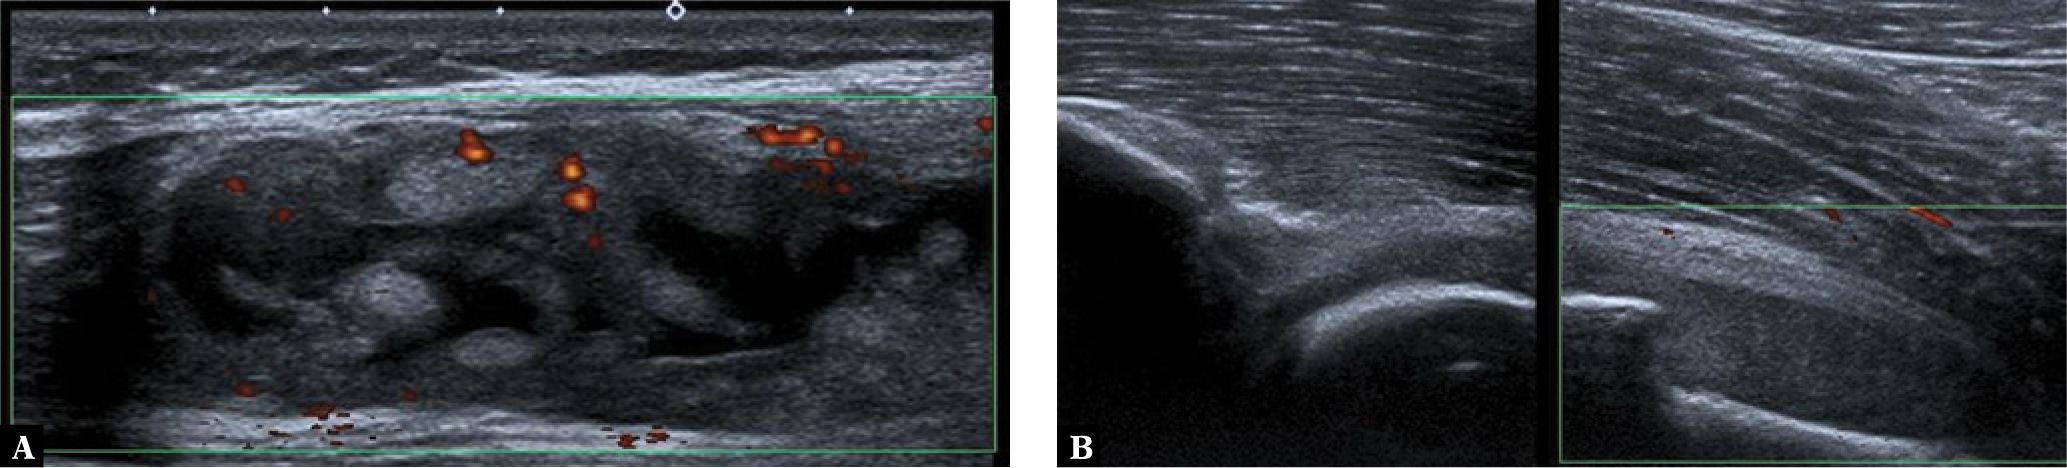

The disease tends to begin with monoarthritis, usually of the lower limb. Most commonly affected are the knee and hip (Fig. 2, Fig. 3). Characteristic for the early phase of this disease is also inflammation of the metatarsophalangeal (MTP) and interphalangeal (IP) joints of the first toe (Fig. 4). Involvement of the joints of the upper limbs is sporadic; however, in such cases the sterno-clavicular joint may be the first affected in JAS. Sometimes the disease may start with eye inflammation.

Ultrasound in a 17-year-old girl with JAS: A. an image of the sagittal knee suprapatellar recess shows effusions and extensive synovial hypertrophy with mild vascularization; B. thickened, avascular synovium in the hip joint

Hips MRI, T2-weighted fat-sat suppressed (FS) images in axial (A) and coronal (B) planes in a 10-year-old boy with JAS shows right joint synovitis and mild BME in the femoral head and acetabulum